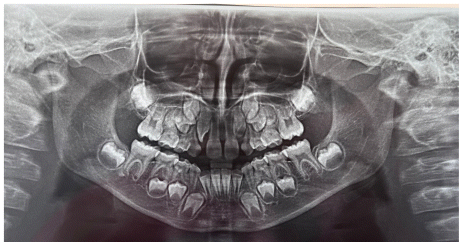

Case 3

The patient was a 6-year-old female presenting with a Class III dento-skeletal malocclusion associated with anterior crossbite in the early mixed dentition (Figures 20–26). Baseline diagnostic records included orthopantomography, latero-lateral cephalometric radiography with cephalometric analysis, and extraoral and intraoral photographs. Clinical examination revealed a flat-to-slightly convex facial profile with sagittal skeletal discrepancy and negative overjet (Tables 5, 6). The treatment consisted exclusively of functional orthopedic therapy using the AMCOP® TC appliance, worn throughout the night and for one additional hour during the day, for a total duration of 24 months. At the end of active treatment, complete correction of the anterior crossbite was achieved, with normalization of overjet and overbite and establishment of a Class I dental relationship. A long-term follow-up evaluation performed at the age of 12 years, in complete permanent dentition, confirmed the stability of the results, showing a well-maintained anterior dental seal and a stable Class I occlusion. The AMCOP® TC appliance was continued as nighttime retention only, supporting neuromuscular balance and occlusal stability throughout growth.